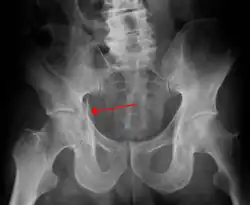

Posterior wall fracture fixed with screws and plate -

| Posterior wall | This is the most common variety of acetabular fracture. It typically occurs due to dashboard injury; when a person travelling in a vehicle involved in a head-on collision, the force applied over the flexed knee travels along the femur bone to the head of the femur, breaking the posterior wall of the acetabulum. The head of the femur is dislocated outside the joint. | T shape | When a transverse fracture also had a vertical fracture line, it is called a T shape fracture. Here the innominate bone is broken in such a way that all three parts of it, the ilium, the ischium and the pubis are separated from one another. This is a three part fracture. Though both columns are broken, the weight bearing dome is still attached to the main part of the ilium and hence it is not a true fracture of both columns.

| Posterior column | As with posterior wall injury, this also typically occurs due to dash board injury. | Posterior column + Posterior wall | These fractures are extensions of elementary fractures. With the involvement of the posterior wall, the difficulty in treatment increases. These fractures are rarely amenable to non-surgical treatment. Due to posterior wall fracture, the hip is usually dislocated posteriorly, requiring immediate reduction of dislocation and surgical reconstruction after a few days.

The final management depends on the size of the fragment(s), stability and congruence of the joint. In some cases traction for six to eight weeks may be the only treatment required; however, surgical fixation using screw(s) and plate(s) may be required if the injury is more complex. The latter treatment will be called for if bone fragments do not fall into place, or if they are found in the joint, or if the joint itself is unstable.